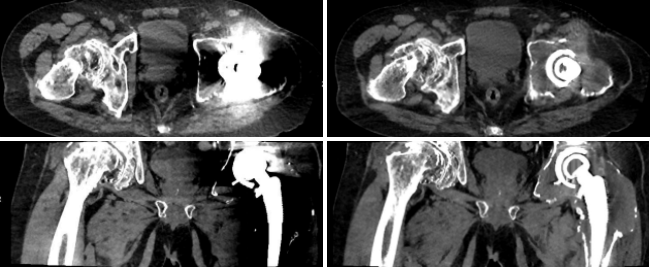

7、去金屬偽影應(yīng)用

病例一 男,76歲, 髖關(guān)節(jié)置換術(shù)后翻新術(shù)前檢查

SEMAR OFF SEMAR ON

左側(cè)髖關(guān)節(jié)內(nèi)見(jiàn)置換物影,未使用SEMAR技術(shù)前見(jiàn)大片低密度偽影,周圍組織顯示不清。使用SEMAR技術(shù)去金屬偽影處理后,可見(jiàn)股骨頭及髖臼膨大,骨質(zhì)變薄,其內(nèi)見(jiàn)異常密度軟組織包繞置換物。

對(duì)于體內(nèi)金屬所產(chǎn)生的偽影,常規(guī)CT減輕其影響的辦法是:薄層掃描抑制其部分容積效應(yīng),選擇較高千伏值減其射線硬化影響等,但無(wú)法根本解決。所以目前術(shù)后檢查首選X線檢查,對(duì)CT與MR為檢查相對(duì)禁忌癥。

640層寬體探測(cè)器CT搭載了最新一代單能金屬偽影消除技術(shù),無(wú)需采用雙能采集,亦可在不知道病人是否有金屬偽影的前提下,后期進(jìn)行去金屬偽影重建。從而有效改善金屬物體和周圍組織的成像情況, 得到更加準(zhǔn)確的診斷結(jié)果。